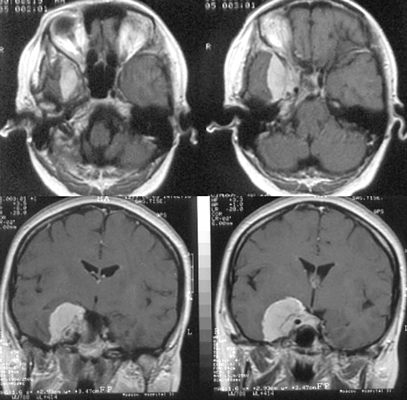

Конвекситальные менингиомы

К конвекситальным относят менингиомы, исходящие из ТМО наружной поверхности мозга, не связанные с верхним сагиттальным синусом и его боковыми лакунами (рис. 1). Они составляют 23% внутричерепных менингиом и делятся по анатомическим областям на лобные, теменные, височные и затылочные. Изредка встречаются внутрикостные (интраоссальные, оссальные) и эктопические менингиомы.

Рисунок 1. Конвекситальная менингиома левой теменной области. МРТ, Т1-взвешенные изображения до (вверху) и после (внизу) контрастного усиления. Несмотря на большие размеры, опухоль не имеет отношения к верхнему сагиттальному синусу